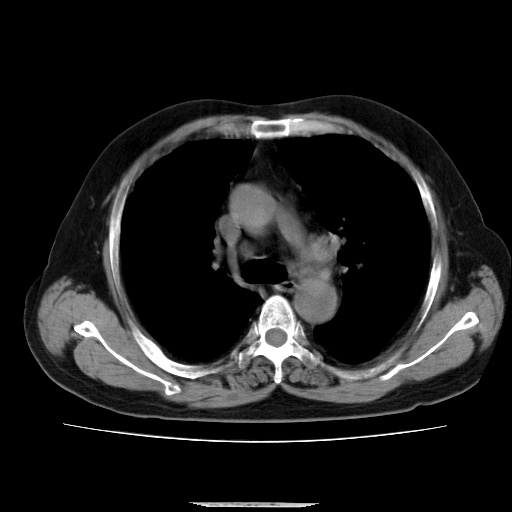

患者,男51岁,反复咳嗽多年,加重10余天,自觉精神不振,无发热,无尿频、尿急及排尿不畅,最近体重有减轻(具体不祥),化验:血常规正常,血糖正常,转氨酶不高,乳酸脱氢酶轻度增高(具体记不得了)

双肺多发结节影,以肺周围分布较多,纵隔淋巴结肿大,考虑双肺转移瘤可能性大。

另胸椎旁改变考虑神经鞘瘤可能性大

1.双肺散在分布小结节影 气管旁淋巴结肿大 中叶背部有胸膜增厚胸膜反应 双侧胸腔积液 考虑转移性肺癌

2. 支持胸椎旁改变考虑神经鞘瘤

本例的特点:结节弥漫多发,但所有的结节都没有一个比较清楚的境界,其边界都比较模糊;

其分布并不像转移瘤那样主要分布于肺的外围,而是中心部位较外围的要多;

印象:把炎症性病变放在首位;

考虑 1、慢支并感染; 2、转移待排----右下肺那个有小泡的要小心一些;

建议正规抗炎两周后复查;如有条件请查肿瘤系列;